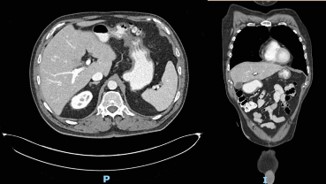

The patient followed an excellent clinical course, with full resolution of the symptoms after three months of treatment. The follow-up CT scan obtained three months (Figure 3) and six months (Figure 4) after admission revealed the complete dissolution of the bezoar. Annual clinical follow-up was performed until June 2025, with no recurrence of symptoms of bezoar reformation.